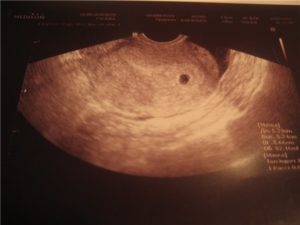

Так на УЗИ выглядит пустое плодное яйцо.

Пустое плодное яйцо – это по сути беременность, которая не начала развиваться. Процесс развития прекратился еще до этапа формирования эмбриона. Причин такого нарушения достаточно много.

На ранних сроках крайне сложно выявить пустое плодное яйцо. Так как размеры эмбриона очень малы и его можно просто не заметить. Только по прошествии 5 недель, появляется возможность определить отсутствие плода.

Только на шестой неделе беременности пустое плодное яйцо можно диагностировать с помощью УЗИ. Оно проводится в любом случае, чтобы определить месторасположение плода, а также исключить внематочную беременность.